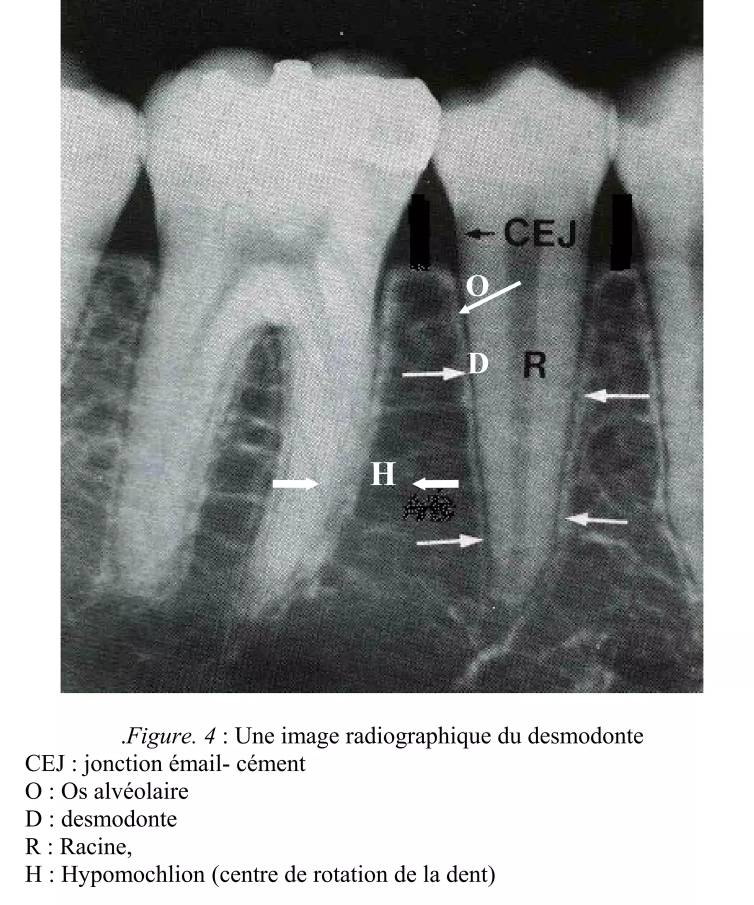

3.4. Aspect radiographique

À la radiographie conventionnelle, le desmodonte se visualise comme une ligne radioclaire fine et régulière séparant :

- La surface radiculaire (radiopaque)

- La lamina dura (ligne radiodense longeant l’alvéole)

Selon PRICHAUD, une image d’épaisseur régulière est un signe de normalité. À l’inverse :

- Un élargissement de l’espace desmodontal évoque une surcharge occlusale, un traumatisme ou une parodontite apicale

- L’absence de l’espace desmodontal signe l’ankylose dento-alvéolaire